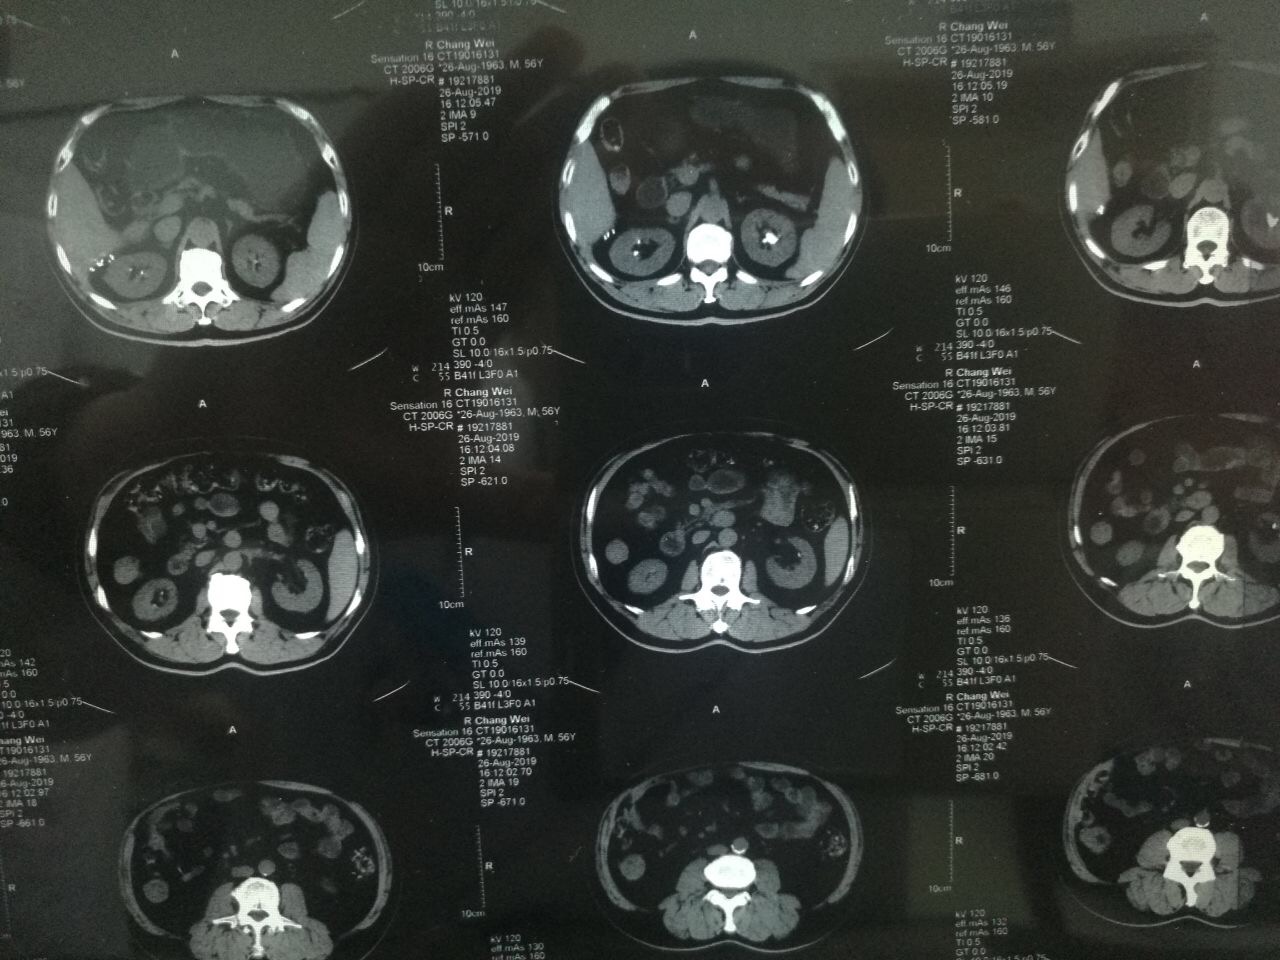

?2019年8月22日,家住陕西永寿县的一岁半幼儿笑笑(化名)突然出现阵发性哭闹,且伴有腹痛、小便不畅、尿色深黄浑浊等症状,奶奶遂带其前往永寿县医院诊治,县医院诊断为“包皮炎”,并给予局部涂擦碘伏。可没想到5天后,笑笑再次哭闹不止,且完全不能自解小便,尿液自尿道溢出,下腹胀满。再次来到县医院治疗,经过CT及超声检查显示,孩子尿潴留,尿道结石,肾结石。由于患儿年纪小,病情更为复杂和紧急,经推荐笑笑从县医院转入男同视频 泌尿外科进行治疗。转入男同视频 时,患儿腹胀如鼓,时不时有尿液自尿道滴出,哭闹异常剧烈。见此情景,泌尿外科张争春医生立即带领王卫妮护士长给患儿进行导尿,但因结石恰好卡在尿道,导尿管难以插入,张争春医生在患儿的哭闹声中,经过多次努力,终于将导尿管成功插入,暂时缓解了患儿的危急症状,也为后续的治疗创造了机会。